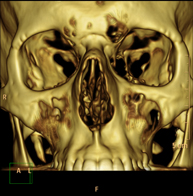

- TC Macizo facial

Prueba radiológica que consiste en obtener imágenes del macizo facial (cara) de alta definición anatómica mediante el empleo de un equipo de TC (Tomografía Computarizada). Indicaciones: tumores, cirugía plástica.